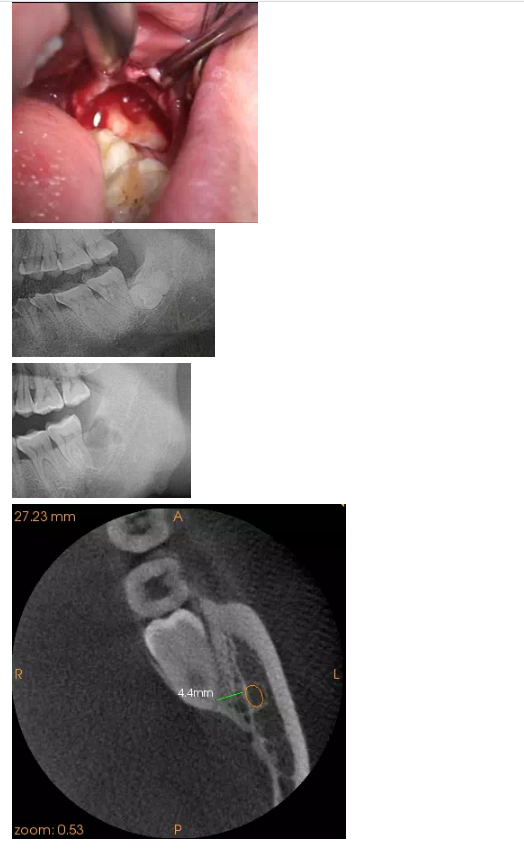

一位患者要求拔左側(cè)智齒,全景片顯示:根尖三分之一處于下牙槽神經(jīng)管重疊,CT顯示整顆牙都位于下牙槽神經(jīng)管的舌側(cè),最近的距離位為4.4mm,這給整個術(shù)前診斷起了決定性的作用。